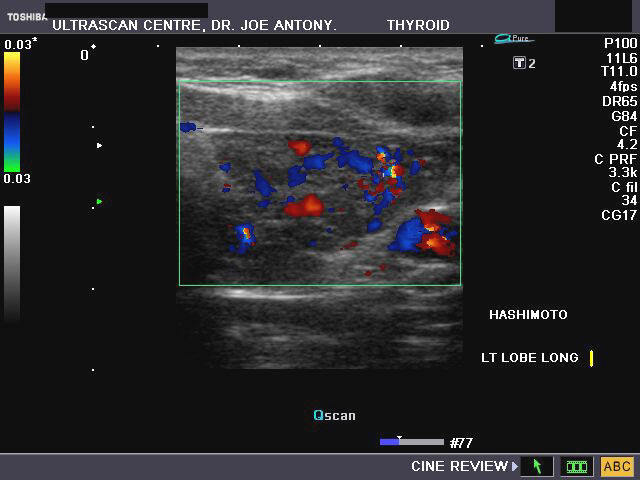

Hashimoto's thyroiditis

Sonography of the thyroid gland in this middle aged female patient reveal: 1) hypoechoic thyroid gland 2) coarse echotexture of the gland 3) fine linear echoes within the thyroid parenchyma s/o fibrosis 4) Color doppler imaging reveals augmentation of the vascularity of the thyroid gland. These ultrasound images are diagnostic of Hashimoto's thyroiditis. Images taken using a Toshiba Nemio- XG color doppler machine. Hashimoto's thyroiditis is often a cause of decreased thyroid function or hypothyroidism and is thus a causative factor in the development of obesity. Both type1 and type 2 diabetes may be associated with Hashimoto's thyroiditis.